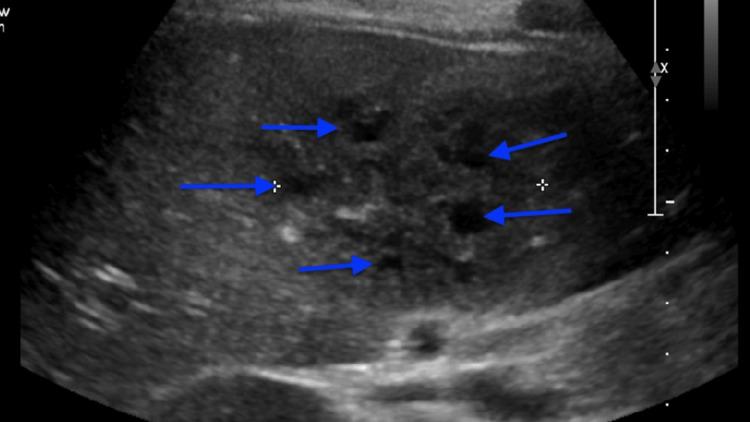

Methicillin-resistant (MRSA) hepatic phlegmon is a rare cause of fever of unknown origin (FUO) in an immunocompetent patient from a high-income country (HIC). MRSA hepatic phlegmon is typically linked to protein malnutrition and chronic gastrointestinal infections in low- to middle-income countries while immunodeficiencies such as chronic granulomatous disease (CGD) are a more common cause in a HIC. Clinical manifestations of hepatic phlegmon can be vague and nonspecific making a complete FUO workup critical during evaluation. We report a case of MRSA hepatic phlegmon in an immunocompetent patient with a nonspecific history and physical exam findings. A 14-year-old male presented with an 11-day history of fever with mild bilateral upper quadrant abdominal pain. The patient also has mild upper quadrant pain with palpation. The patient was diagnosed with a hepatic phlegmon on abdominal ultrasound and computed tomography (CT) of the abdomen. He was started on antibiotics and Interventional Radiology placed drains into the phlegmon and performed vancomycin drain washes. Inflammatory markers were initially elevated and trended down with interventions. The patient did well with treatment and was back to baseline during outpatient follow-up with the Infectious Disease team. This case illustrates the importance of a complete workup in patients with FUO.